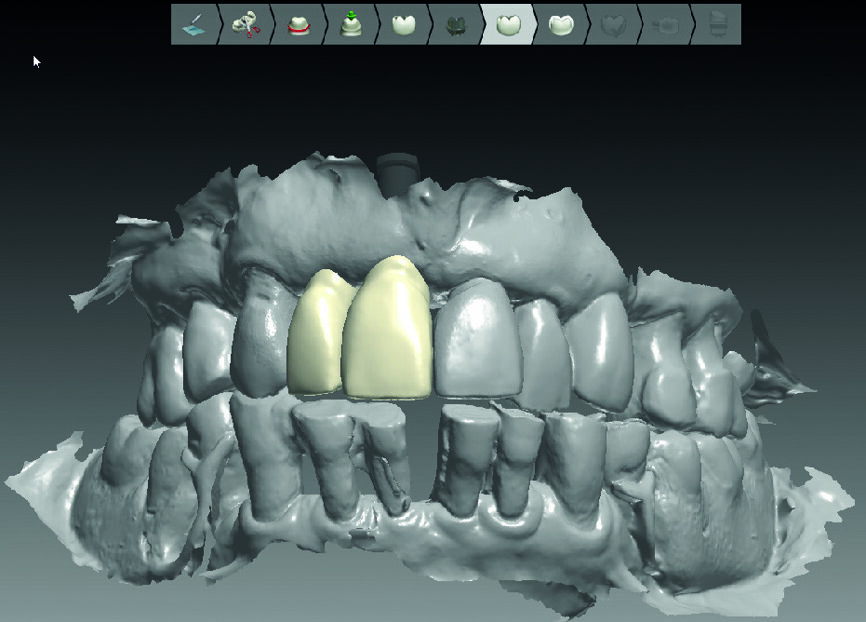

Des empreintes optiques (maxillaire, mandibulaire et occlusion) (3Shape) et un cône beat (Gendex) sont réalisés. La planification est alors réalisée à l’aide du logiciel Implant Studio. De son cote, le laboratoire de prothèse (Crown Ceram) prend en charge toute la préparation pré-chirurgicale, à savoir la réalisation du guide chirurgical (Fig. 4) mais aussi les piliers et les couronnes provisoires (Figs. 5a et 5b, 6a et b).

Fig. 4 : Guide chirurgical avant impression.

Figs. 5a et b : Design des couronnes provisoires virtuelles et leur piliers provisoires en transparence.